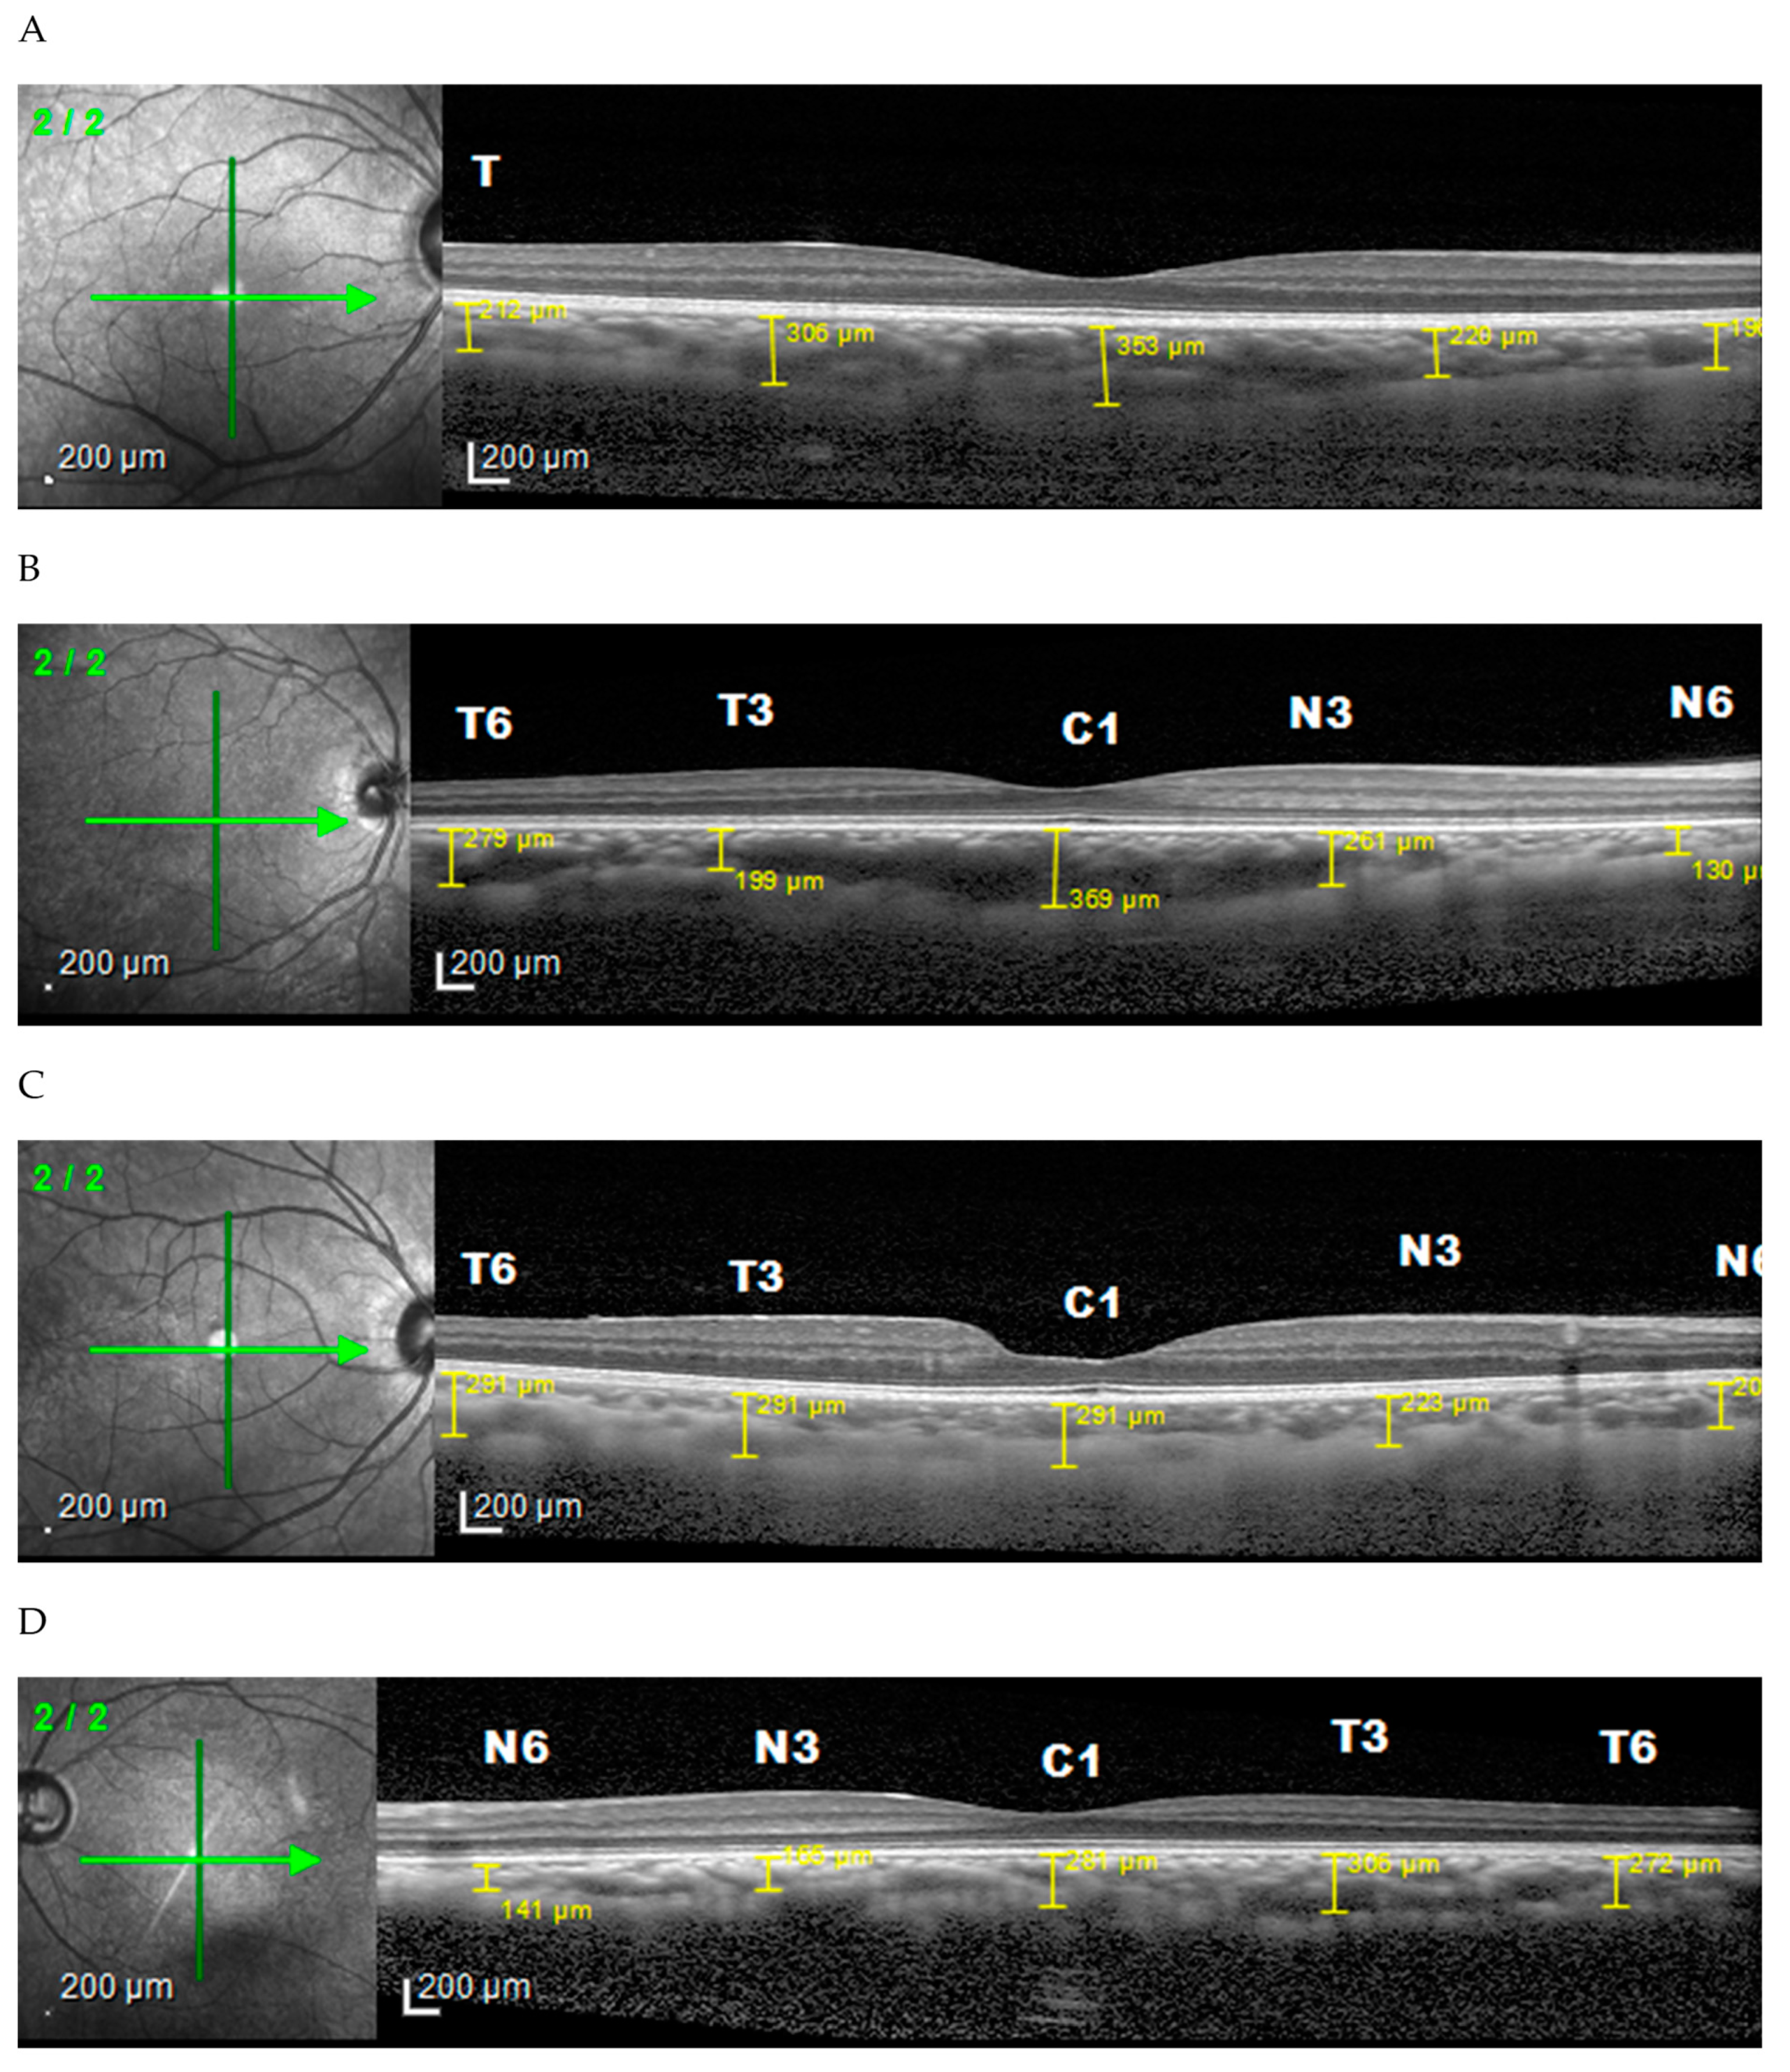

3. Results